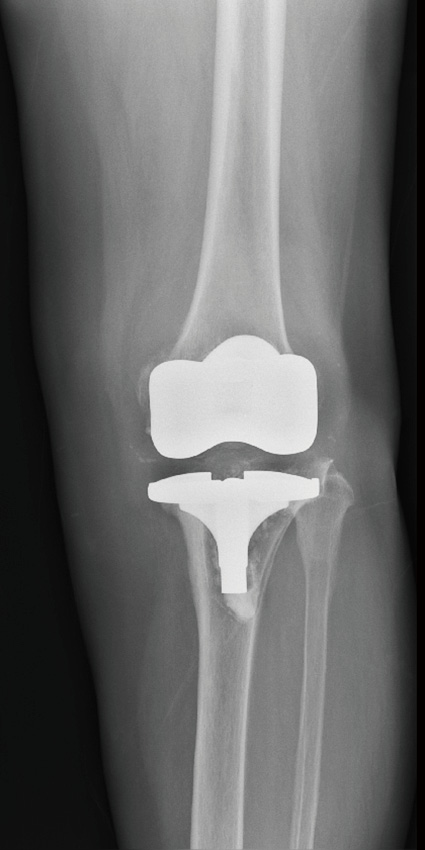

单髁膝关节置换术后8年,塌陷,接受全膝关节表面置换术

单髁置换

膝关节内侧间隙狭窄,适合单髁置换,手术后恢复快,

关节活动最大限度保留